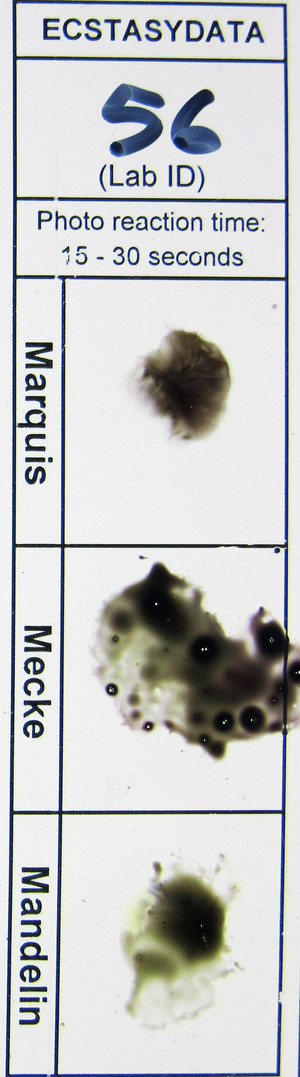

MDMA (74816)

ID: 4621

| Lab's ID: | 20160700056 |